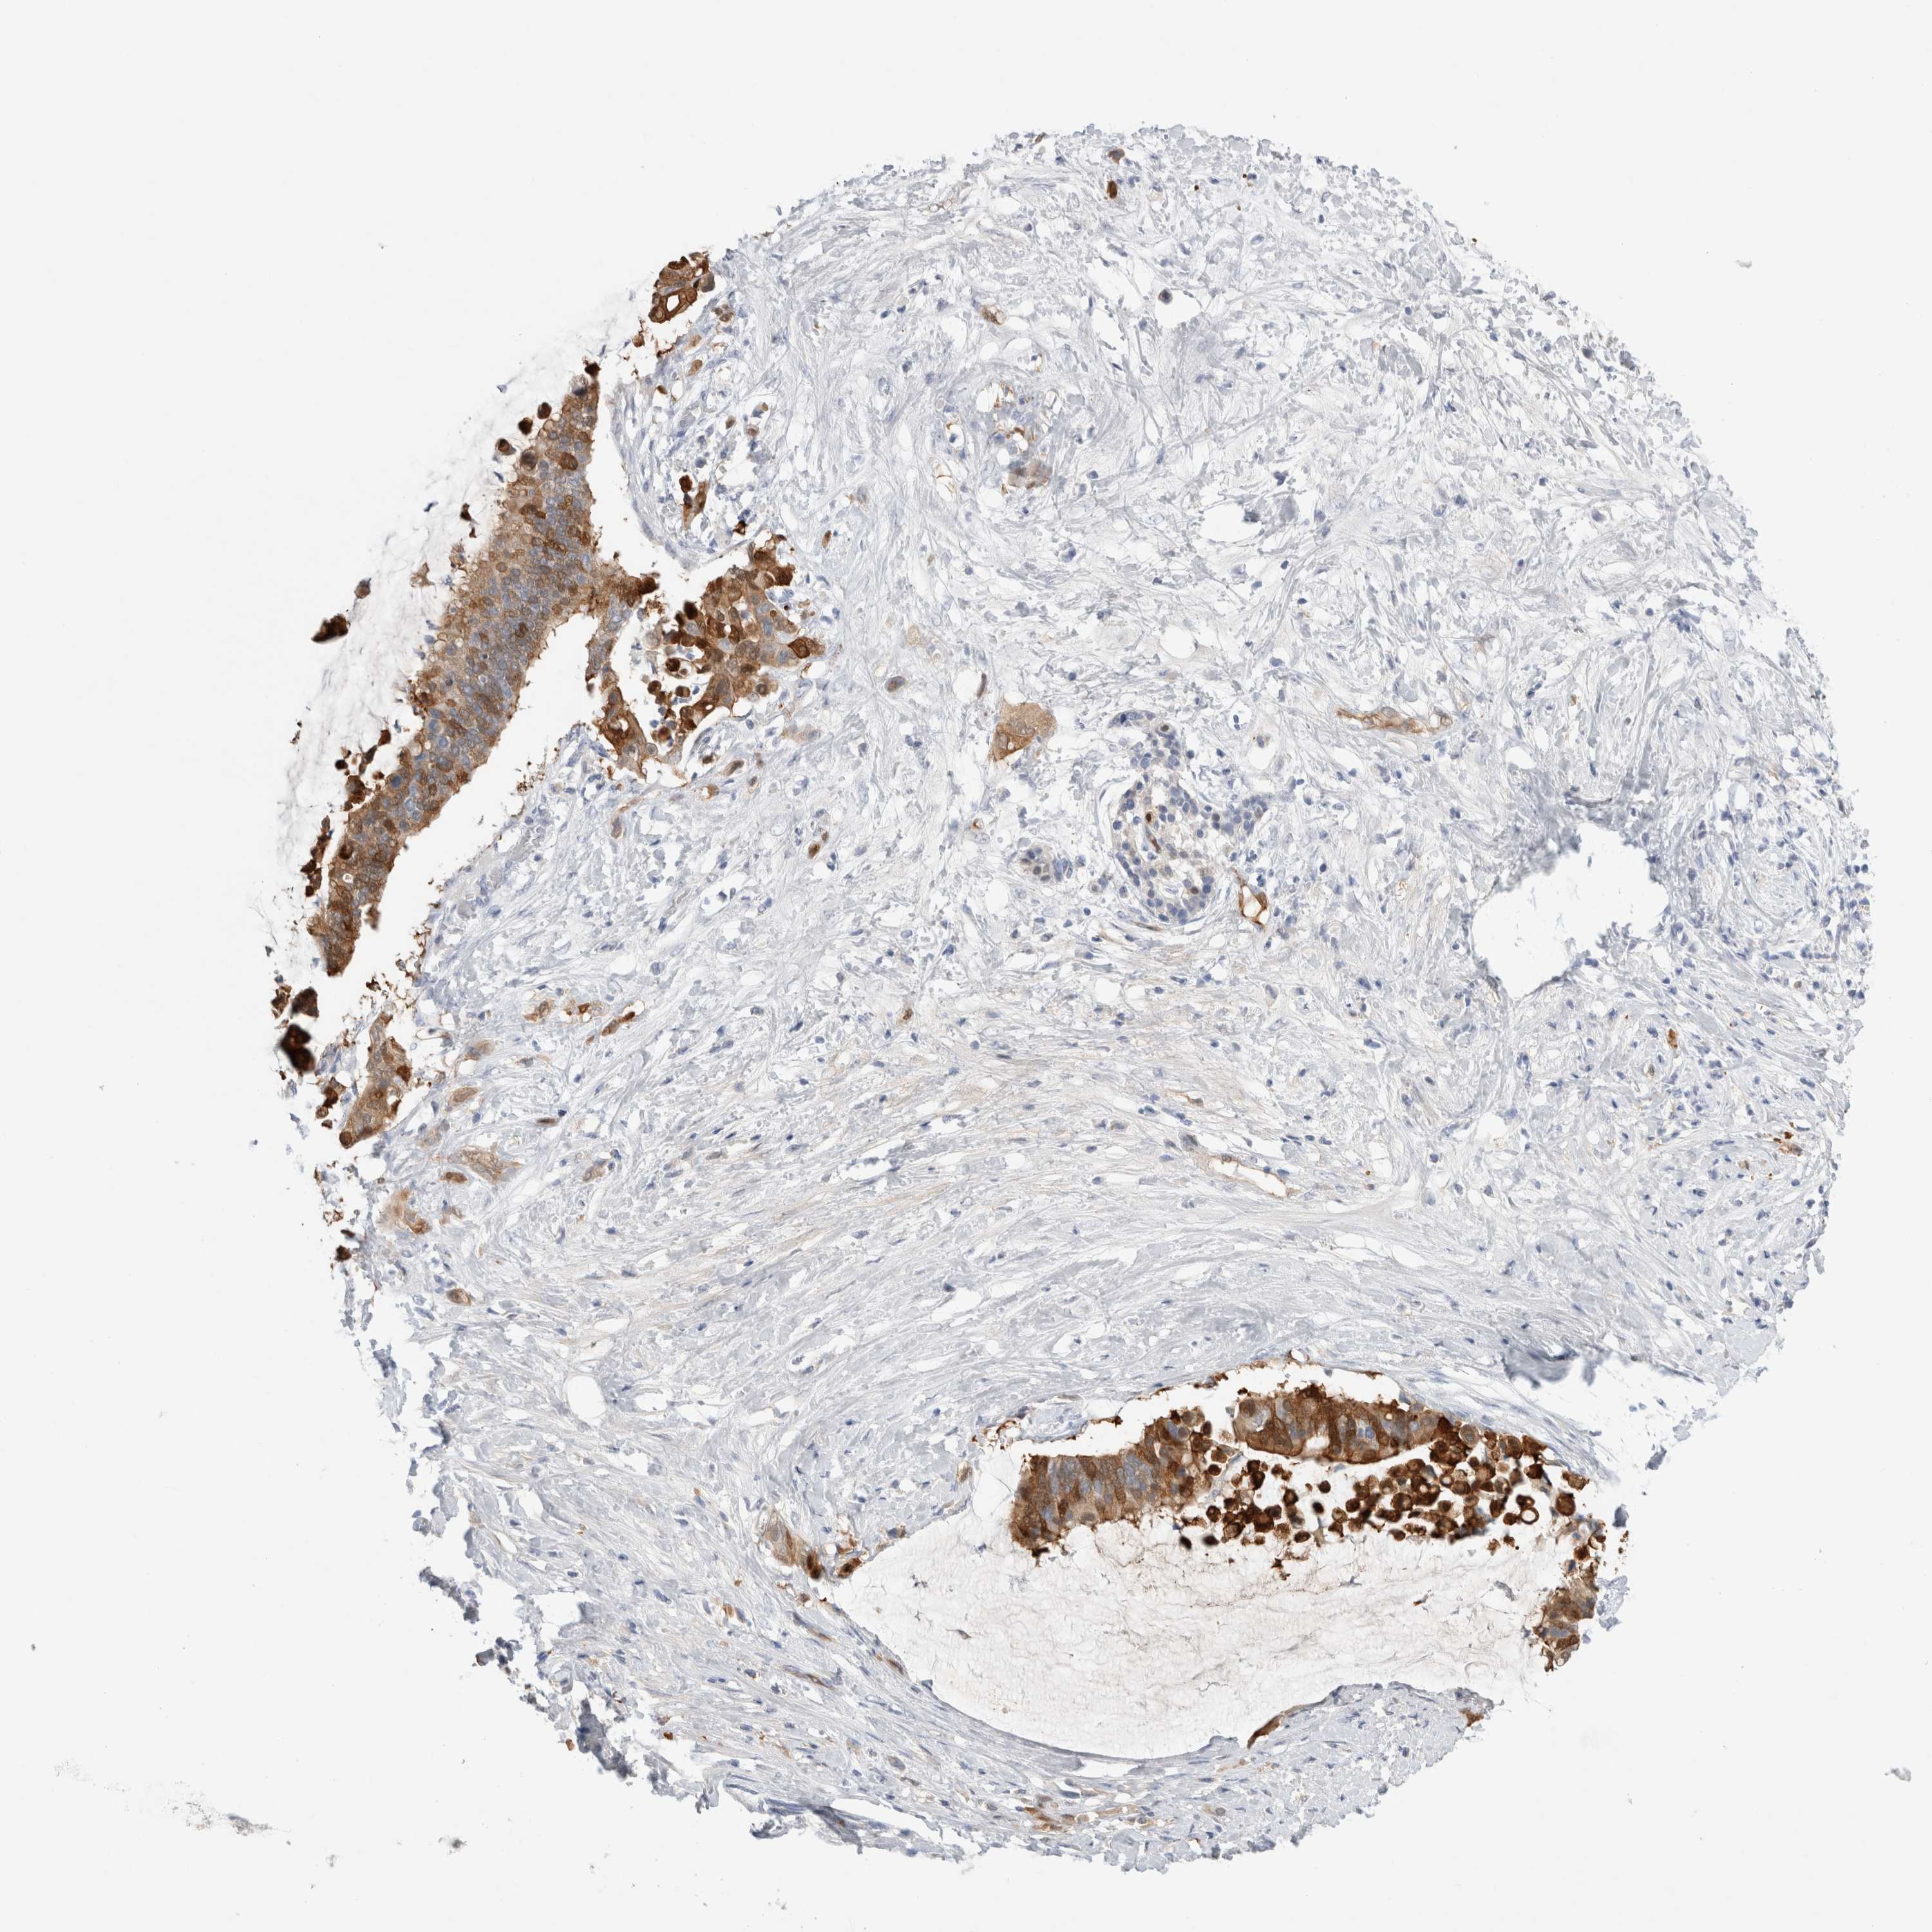

PANCREATIC CANCER - Protein expressioni

A mouse-over function shows sample information and annotation data. Click on an image to view it in a full screen mode. Samples can be filtered based on level of antibody staining by selecting one or several of the following categories: high, medium, low and not detected. The assay and annotation is described here.

Note that samples used for immunohistochemistry by the Human Protein Atlas do not correspond to samples in the TCGA dataset.

Antibody stainingi

Antibody staining in the annotated cell types in the current human tissue is reported as not detected, low, medium, or high, based on conventional immunohistochemistry profiling in selected tissues. This score is based on the combination of the staining intensity and fraction of stained cells.

Each image is clickable and will lead to virtual microscopy that enables deeper exploration of all samples and also displays staining intensity scores, fraction scores and subcellular localization as well as patient and tissue information for each sample.

Antibody HPA019832

Antibody HPA024338

Adenocarcinoma, NOS